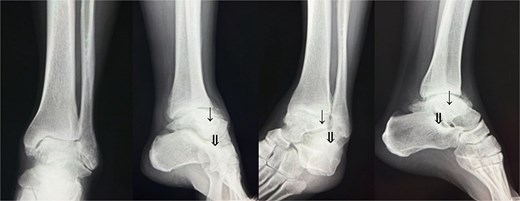

Preoperative radiographs and computed tomography (CT) demonstrated complete loss of the tibiotalar joint space, talar subluxation, and extensive osteophyte formation consistent with end-stage post-traumatic osteoarthritis (Figs 1 and 2). After informed consent and institutional review board approval (IRB number #20251001), the patient underwent arthroscopic ankle arthrodesis.

Preoperative radiological imaging: CT finding. The articular surface is completely collapsed and obliterated (1: white arrowhead). The talus is positioned in a subluxated state, and multiple osteophytes are observed on the medial, lateral, and posterior aspects (2–4: black arrowhead / circle with dotted outline). Both radiographs and CT images demonstrated end-stage osteoarthritis of the ankle, characterized by complete collapse of the articular surface and multiple osteophytes along the anterior, lateral, and posterior aspects of the joint (circle with dotted outline).